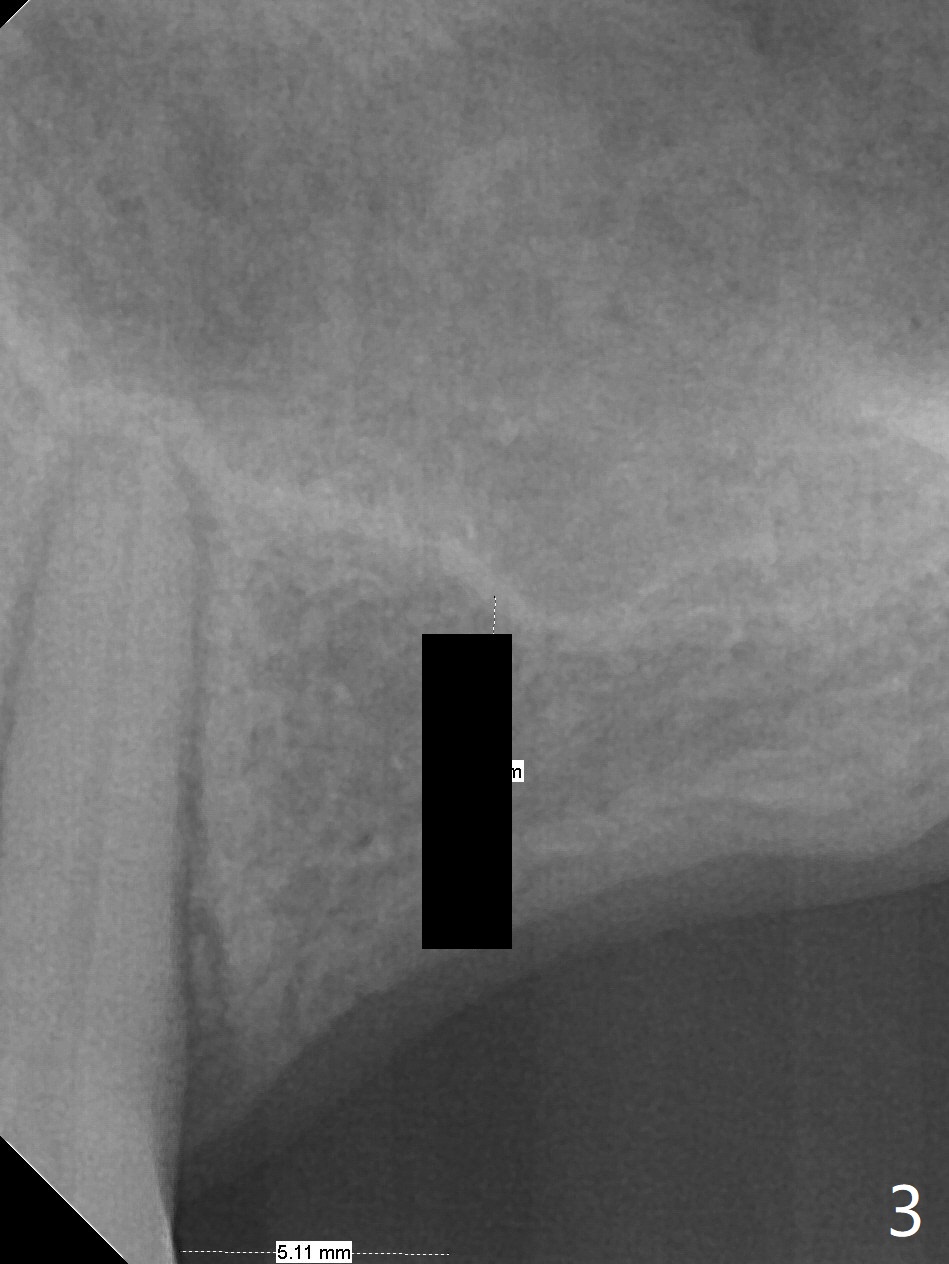

A 57-year-old woman has lost #14,15 and 18 for a while (Fig.1). Because of fear, an implant will be placed at #14 first (Fig.2). After use of Magic Drill for 5 mm (Fig.3), Magic Lifter will be used for lift (Fig.4). Following placement of PRF membrane (Fig.5 blue) and Vanilla Graft (red circles), a dummy implant is placed for additional lift (Fig.6 green). With placement of a larger and probably longer definitive implant, the graft may migrate distal due to gravity in sleep (Fig.7 arrow). In a few months, the bone height at #15 may increase to facilitate implant placement at #15.